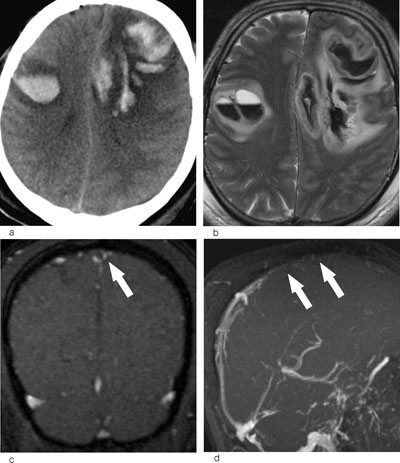

Et typisk bildediagnostisk tegn ved cerebral venetrombose er en fyllingsdefekt i venesinus (fig 1). Disse fyllingsdefektene er hypertette på CT. I sinus sagittalis superior vil fyllingsdefekten ofte ha en trekantet form. På MR vil signalet i tromben variere med alderen (fig 2). Trombene kan også strekke seg retrograd fra venesinus og inn i de kortikale venene. Sekundære forandringer til sinusvenetrombose er hjerneødem og venøse infarkter, typisk beliggende subkortikalt og kortikalt (fig 3). I motsetning til arterielle infarkter vil de venøse ikke følge forsyningsområdene for de store cerebrale arteriene, en annen forskjell er større ødem ved venøse infarkter (18). Venøse infarkter vil ofte være hemoragiske, og på såkalte hemosekvensbilder vil man se blodproduktene som områder med lavt signal.

Ved bildediagnostikk av cerebral venetrombose er det viktig å være oppmerksom på noen fallgruber. Det er en betydelig grad av anatomiske variasjoner i de durale venesinuser, dette gjelder særlig i sinus transversus. Hos vel to tredeler av alle mennesker er høyre sinus transversus større enn venstre. Sinus transversus er hypoplastisk eller manglende på den ene siden hos nær en tredel, vanligvis på venstre side. En manglende fremstilling av sinus transversus må derfor ikke uten videre tolkes som en okklusjon fremkalt av trombe (fig 4). Pacchioni-granulasjoner i venesinuser er en normalvariant (19). Disse granulasjonene kan bli opptil et par centimeter og delvis okkludere venesinus (fig 4). De kan skilles fra tromber ved at de har en typisk lokalisasjon ved innmunningen av Labbes vene i sinus transversus og ved at signalmønsteret er annerledes.